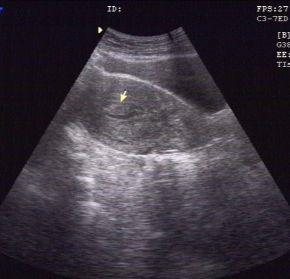

子宫内膜息肉的无创检查,首选妇科超声检查,推荐经阴道超声(有*生活性**史的女性)或经直肠超声(无*生活性**史的女性)。一般妇科超声检查的时间选择月经周期的第5-7天(早卵泡期)为最佳。但即使超声有上述提示子宫内膜息肉,并不等于确诊。